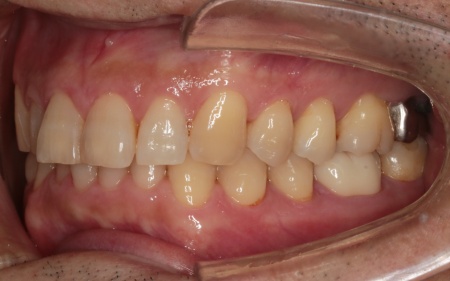

治療後